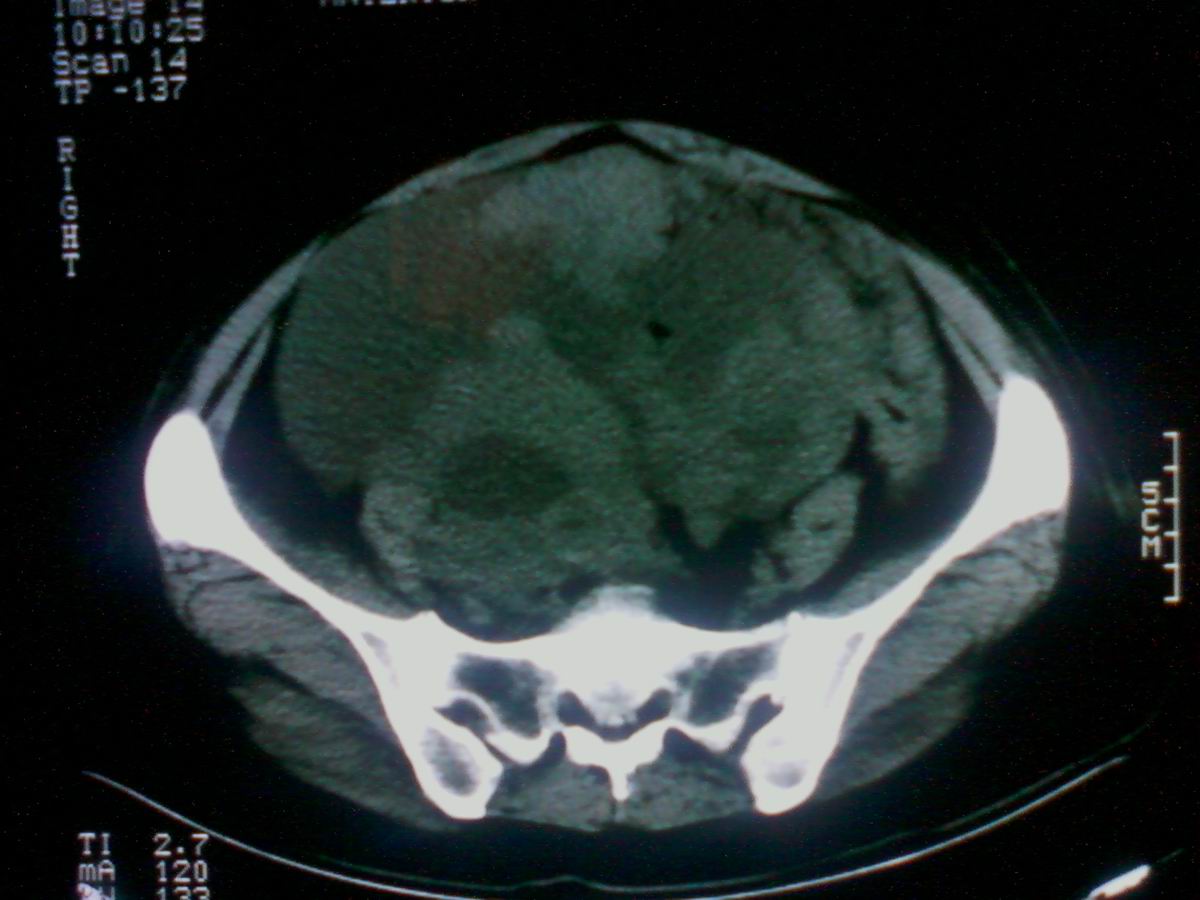

标题: CT25799:女性患者,45岁,腹胀,上腹部疼痛来诊,B超示盆腔 [打印本页]

标题: CT25799:女性患者,45岁,腹胀,上腹部疼痛来诊,B超示盆腔

考虑卵巢癌伴腹水

1)考虑卵巢恶性肿瘤。2)腹水。